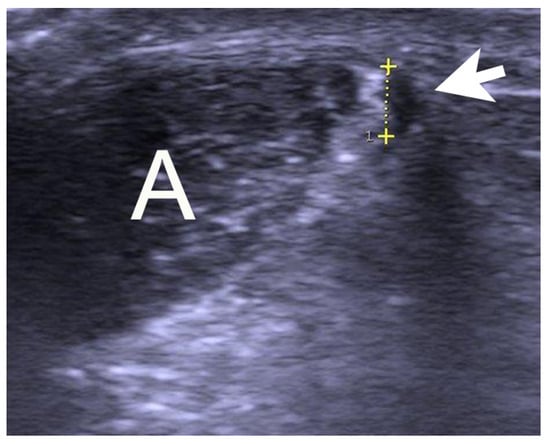

Patients were examined and operated on at Capio Orthocenter Skåne in Malmö, Sweden. Clinical examination demonstrated a thickening of the Achilles midportion with tenderness located on both the ventral and the medial side of the tendon thickening in all cases. High resolution gray-scale US + CD (S-500, Siemens AG, Germany) using a linear multifrequency (8–13 MHz) probe showed a thickened Achilles midportion (>7 mm) with irregular tendon structure. On the medial side of the Achilles midportion, there was a wide or thick plantaris tendon (Figure 1). There was also a localized high blood flow outside and inside the regions with structural tendon changes.

Figure 1. Gray-scale ultrasound picture of a patient suffering from midportion Achilles and plantaris tendinopathy showing a widened plantaris tendon (arrow/yellow scale) located close to the medial side of the Achilles tendon A.